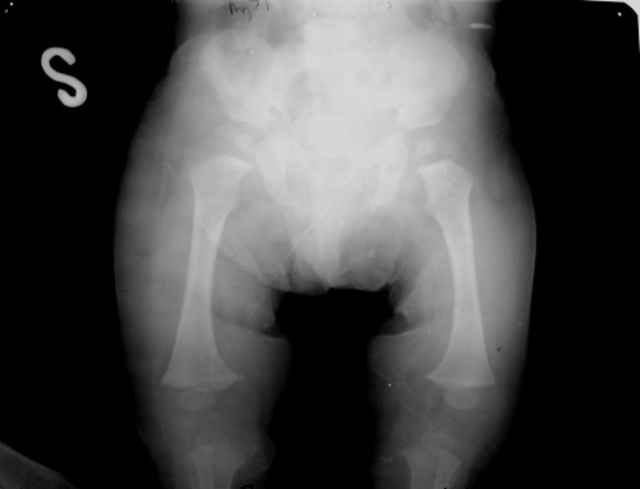

Мальчик, 5 лет. Гипохондроплазия. Генетическая предрасположенность к нарушению физического развития. Ребенок от I беременности, протекавшей нормально. ТОРЧ-негативный. Неврологических расстройств нет. Семейный анамнез: средний рост мужчин в семье 150 см, антропологические особенности - короткие конечности, длинное туловище, крупный череп. Вес 15 кг, рост 92 см.Тактика лечения? Заранее благодарю! С уважением,А.В.Владзимирский